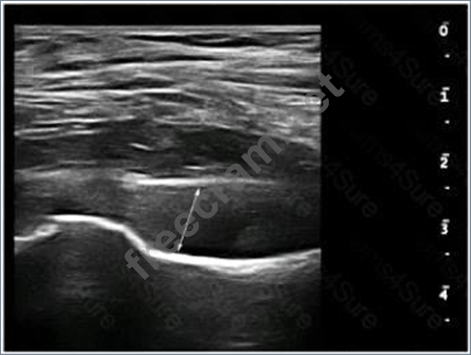

What is the MAXIMUM normal dimension of the structure indicated by the line in this image?

Question 25: What is the MAXIMUM normal dimension of the structure indica...